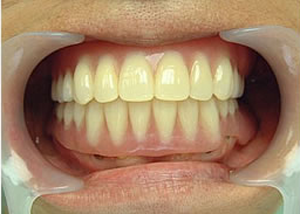

16.上は仕上がりが入り、下は仮歯です。

19.下は作った最終本物の歯が入りました。

これで治療終了。

開口器を入れた口元

治療完了

平成21年1月29日

(治療期間:1年7ヶ月)